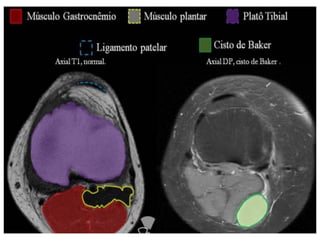

T1 NO JOELHO

 Utilizada para verificar anatomia muscular, óssea e

principalmente menisco.

 A gordura fica branca, fornecendo contraste para o

tendão e o músculo.

CASO CLÍNICO: CISTO DE BAKER

Caracteriza-se por uma hipertrofia (acúmulo de líquido)

da bolsa sinovial que separa o tendão da porção medial

do gastrocnênio do tendão semimembranoso. Causa:

atrito dos tendões.